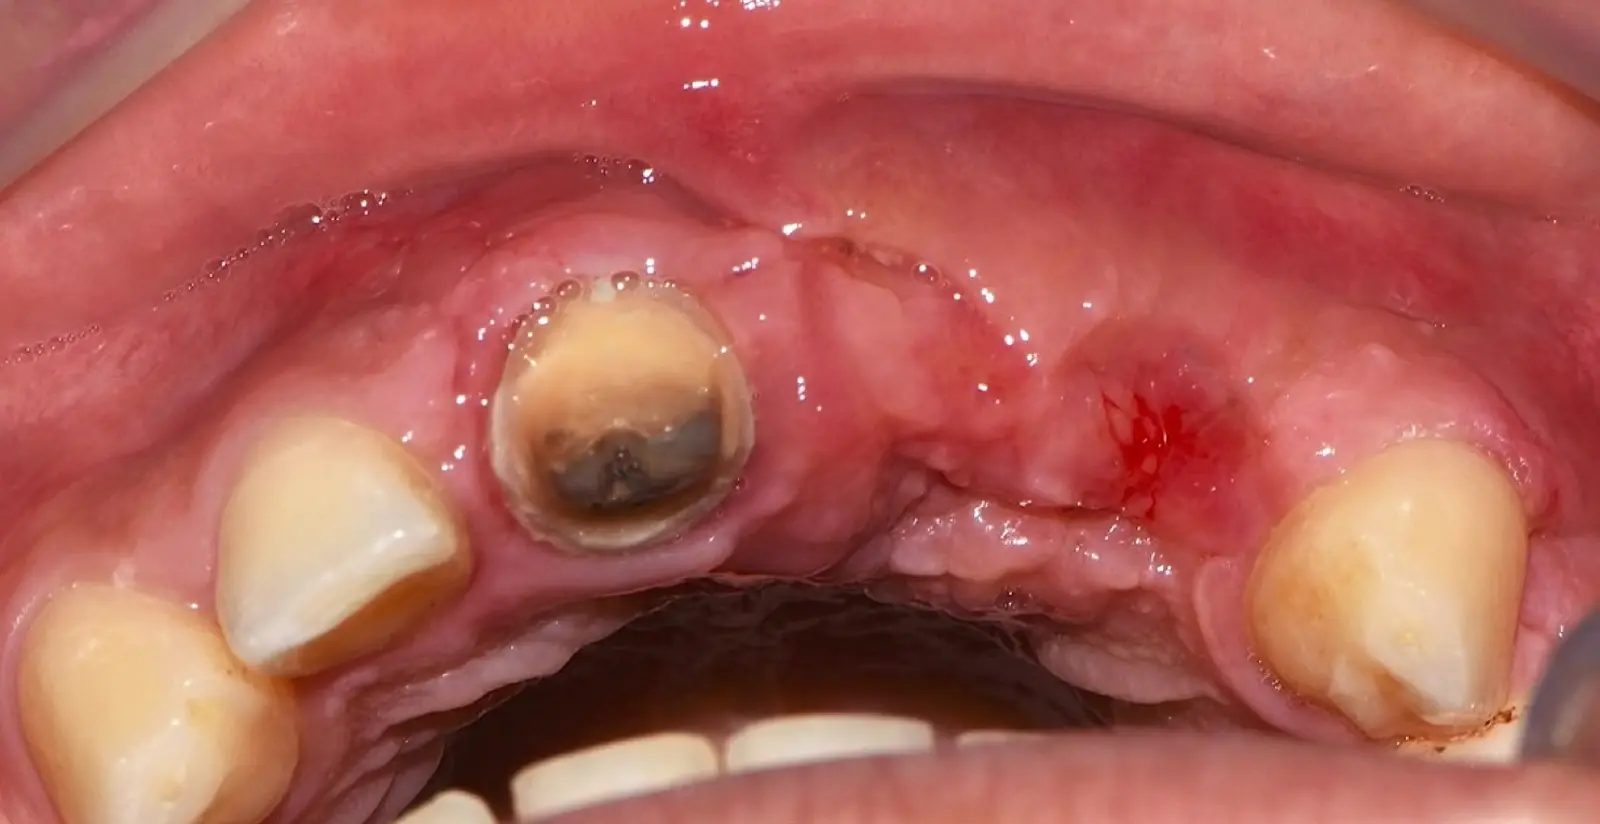

Paciente de sexo femenino de 36 años de edad, llega a la consulta por presentar una restauración protésica inadecuada. En el examen clínico se observa una restauración protésica provisional acrílica sobre las piezas 1.1 y 2.2. Adicionalmente, se aprecia recesión gingival a nivel de la pieza 2.2 y deficiencia horizontal severa de reborde a nivel de la zona edéntula correspondiente a la pieza 2.1. En la evaluación tomográfica se observa ausencia total de tabla ósea vestibular en la pieza 2.2, y se corrobora el déficit en la zona edéntula de la pieza 2.1, para lo cual se indica una reconstrucción de estructuras óseas con hueso en bloque de origen bovino y posteriormente la colocación de implantes dentales.

Figura 46. Control a los 10 días post cirugía.